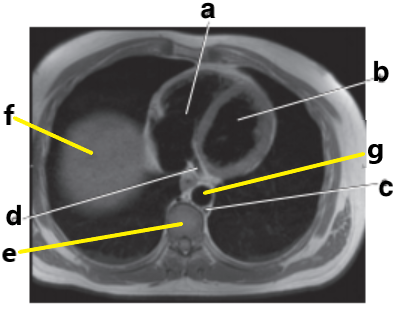

What is letter b ?

Esophagus

Left ventricle

What is letter a ?

Left atrium

Right ventricle

What is letter d ?

What is letter g ?

Right atrium